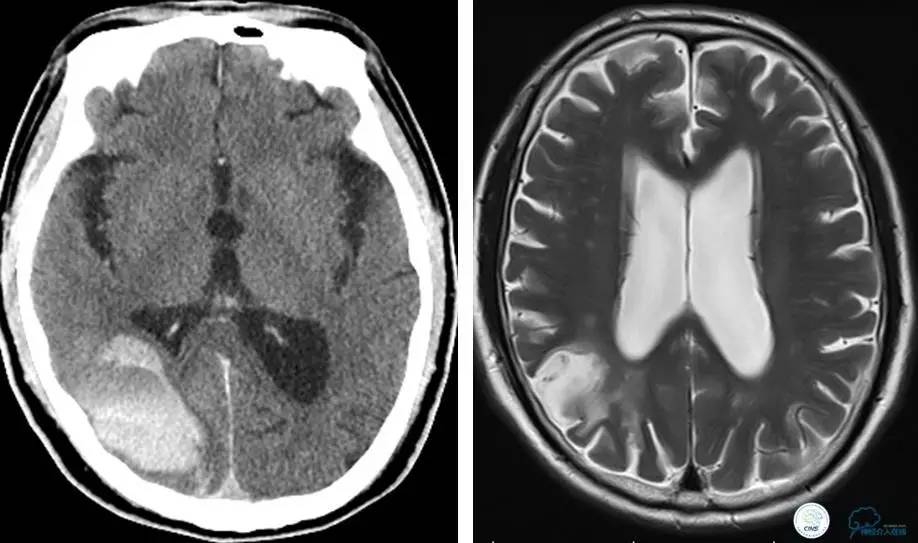

患者:53岁男性,反复脑梗死3个月。

▼给予球囊扩张成形,闭塞段较长,决定药物治疗观察,二期再给予支架治疗。

▼药物治疗1个月,再次发作。再次来我院支架治疗。

▼支架术后,效果好。

因此,某些患者分期治疗也具有合理性。

病例5

患者:49岁男性,左侧偏瘫1个月,药物治疗、康复训练效果不好,转我院,肌力0~1级。

core-clilnical明显不匹配,是介入开通的合适患者。